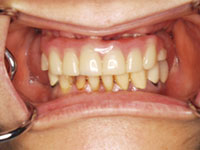

口内写真

歯周病の進行により、上顎の歯は全て抜歯しなくてはならない状態.